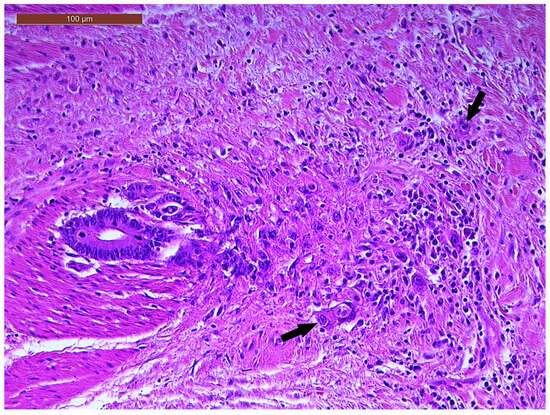

LVI was detected in 31 cases (51.7%), and perineural invasion (PnI) was identified in 20 cases (33.3%) (Figure 1 and Figure 2). EMVI and IMVI were registered in 31 (51.7%) and 21 cases (35%), respectively. Regarding Bd and PDC categories, a significant proportion of tumors were recorded as Bd1, while Bd2 was less common (49 cases; 81.6% vs. 7 cases; 11.7%) (Figure 3); moreover, a large proportion were classed as the PDC1 grade (Figure 4), while the PDC2 grade was less common (55 cases; 91.7% vs. 4 cases; 6.7%). The main clinicopathological characteristics of the study group are summarized in Table 4.

Figure 1. Lymphovascular invasion (arrow) in a ypT3-stage LARC case (H&E staining, 200×).